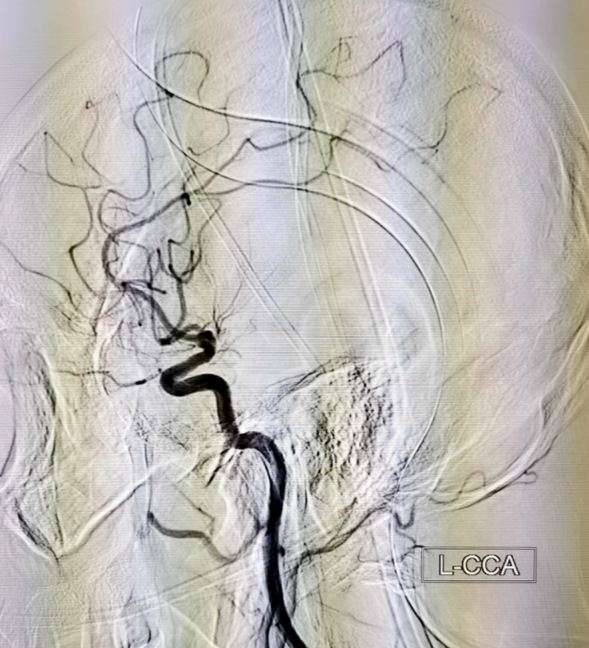

术前左侧颈内动脉正位造影

术前左侧颈内动脉侧位造影

当天15点47分,一位老年男性患者在家中看电视时突发右侧肢体活动不灵,不能言语,家属紧急将其送往我院急诊就诊并联系神经内五科迟景宏主任。16点40分,患者在家属陪同下来到我院急诊。迟景宏主任在紧急查看患者病情并完善相关检查后,果断判断患者为急性大血管闭塞,通过与患者家属交代病情,征得了患者家属的同意,决定对其行静脉溶栓治疗。经验丰富的迟景宏主任判断单一溶栓难以缓解患者大血管闭塞所导致等症状,立即请介入放射科刘琳主任、莫庆国副主任进行会诊,建议桥接取栓。17点25分,患者顺利完成主动脉弓上脑血管造影证实左侧大脑中动脉下干闭塞。根据患者病情,神经、介入团队经商议后决定行BADDASS治疗,三件套组合:BGC+中间导管+长取栓支架,交换8F动脉鞘,引入BGC:8F×95cm;颅内支持导管:5F*125cm;取栓支架:4mm*20mm至远端病变血管,透视下释放取栓支架至病变血栓处,停留8分钟后取出大量血栓,一次取栓成功,达到三级再通。复查造影见左侧颈内动脉、左侧大脑前动脉、左侧大脑中动脉显影正常,血流改善,各分支显影良好,M1段未见明显狭窄,术中复查C臂CT未见颅内出血。19点10分,手术顺利结束,术后患者意识清楚,肢体活动较前明显改善,后经对症及康复治疗,患者于2月1日顺利出院,出院时患者恢复如常。通过医生的准确判断、过硬的医疗技术、团队的紧密配合,患者从入院到成功救治在150分钟内顺利完成。